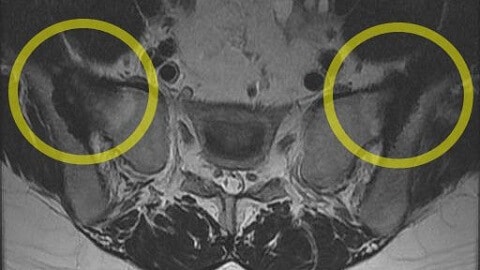

천장관절은 골반의 좌우측에 있는 골반뼈와 천골을 연결하는 관절입니다. 이 관절의 문제는 천골에 통증을 유발할 수 있습니다. 긴 척추를 골반까지 무너뜨려 안정성을 높여주는 관절입니다. 근육과 인대가 단단히 연결되어 있기 때문에 트러블이 잘 생기지 않습니다. 주변 인대가 손상되면 관절이 불안정해져 허리, 엉덩이, 허벅지 주변에 통증을 유발할 수 있다.